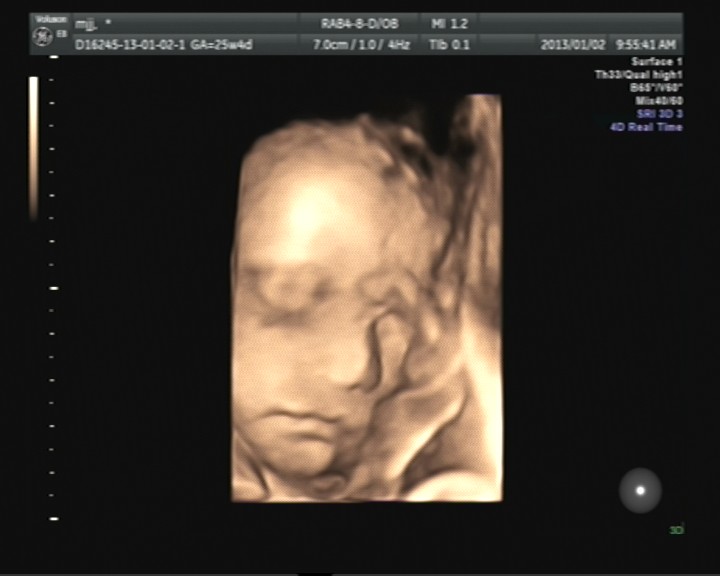

杭州做四维彩超会有副作用吗?近年来医疗设备不断在更新换代,研创了目前先进的四维彩超技术,这是目前世界上比较先进的彩色超声技术,已经广泛应用在各大医学领域上,其诞生为防止胎儿畸形作出了重大的贡献。

四维彩超对胎儿的好处主要包括以下几方面: 1、无辐射:四维彩超主要是采用了人体工程学设计,该检查技术不会存在光波、射线和电磁波等方面的辐射。 2、多角度、多方位:通过检查能够多角度多方位对宫腔内的胎儿生长发育情况进行详细的检查。能够为早期针对胎儿先天性心脏病以及先天性体表畸形提供了准确的科学依据。 3、实时动态活动图像:通过四维彩超检查能够准确的显示出未出生的宝宝的实时动态活动图像,或者其它人体内脏器官的实时活动图像。 4、多方面的应用:可以检查产科、妇科、泌尿科、新生儿、小器官、小器官等等多个领域。 5、拍照:在检查的过程中,能够自动拍照,并且能够制作成VCD,让宝宝拥有蕞完整的0岁相册。 杭州玛莉亚妇产医院--引领全省四维彩超之巅峰 在超声领域,杭州玛莉亚妇产医院具有极高的知名度与美誉度,占据着jue对显着的优势.杭州玛莉亚妇产医院是杭州头家引进四维彩超的医院,目前已拥有五台美国GE高清四维彩超,一台E8高层次四维彩超,引领全省四维彩超之巅峰,刷新了超声领域新运用. 知名专家亲诊,经验丰富,技术精湛 在杭州玛莉亚妇产医院,为准妈妈做检查的,均是资历深厚的专家,经验丰富,技术精湛,超声科带头人钱春蓓主任,更是香港英国胎儿基金产科超声资格认证专家;头批中华胎儿基金会产科超声资格认证专家,从事超声科工作近30年,尤为精通四维彩超的超声诊断,产前胎儿超声筛查诊断. 将热情服务上升为感动服务 杭州玛莉亚妇产医院开展了全程导医陪诊、隐私保护体系、头问负责制、VIP特需门诊;准妈妈课堂等特色服务,将社会-生理-心理三大医疗服务演绎得淋漓尽致.不论在就诊前,就诊中,还是就诊后,每位准妈妈享受到的,将是蕞温馨的服务.